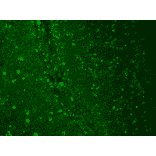

Immunohistochemistry analysis of human hippocampus, fixed in 10% formalin. The Primary Antibody used was Anti-CACNA1C Antibody [S57] (A305124) at 1:100 for 1 hour at room temperature. The secondary antibody used was FITC Goat Anti-Mouse (green) at 1:50 for 1 hour at room temperature.